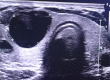

Material and methods: Eighty patients with thyroid nodules who underwent thyroidectomy procedure were divided randomly into two comparable groups, group A subjected to thyroidectomy by using binocular magnification loupe, group B underwent conventional thyroidectomy without using magnification. Patients' demographics, operation time, and postoperative morbidities were recorded. All cases had preoperative and postoperative vocal cords assessment by video laryngoscopy. Pathology, laboratory, and radiology investigations were also conducted.